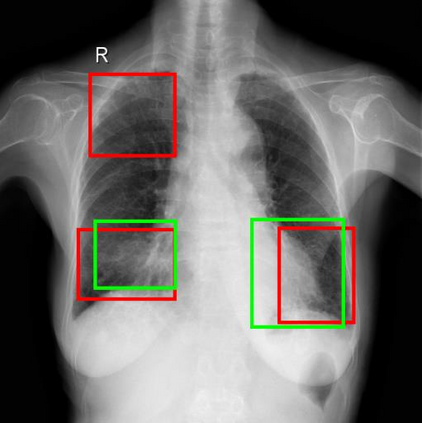

Chest X-ray (CXR) is the most typical diagnostic X-ray examination for screening various thoracic diseases. Automatically localizing lesions from CXR is promising for alleviating radiologists' reading burden. However, CXR datasets are often with massive image-level annotations and scarce lesion-level annotations, and more often, without annotations. Thus far, unifying different supervision granularities to develop thoracic disease detection algorithms has not been comprehensively addressed. In this paper, we present OXnet, the first deep omni-supervised thoracic disease detection network to our best knowledge that uses as much available supervision as possible for CXR diagnosis. We first introduce supervised learning via a one-stage detection model. Then, we inject a global classification head to the detection model and propose dual attention alignment to guide the global gradient to the local detection branch, which enables learning lesion detection from image-level annotations. We also impose intra-class compactness and inter-class separability with global prototype alignment to further enhance the global information learning. Moreover, we leverage a soft focal loss to distill the soft pseudo-labels of unlabeled data generated by a teacher model. Extensive experiments on a large-scale chest X-ray dataset show the proposed OXnet outperforms competitive methods with significant margins. Further, we investigate omni-supervision under various annotation granularities and corroborate OXnet is a promising choice to mitigate the plight of annotation shortage for medical image diagnosis.